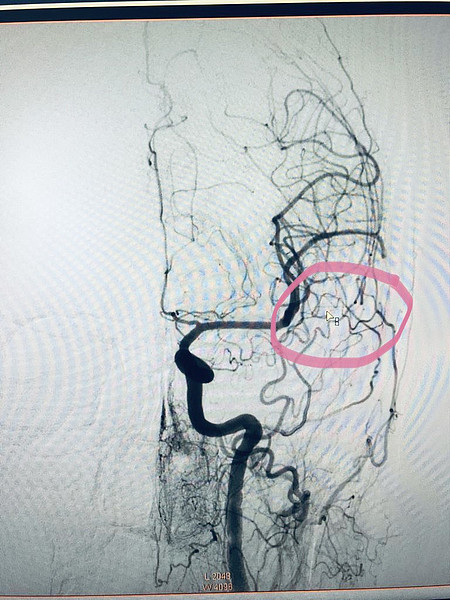

авм1.